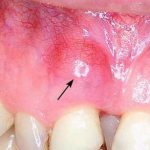

На вид нагноение в мягких тканях может быть разным. Иногда возникает припухлость на десне, охватывающая незначительный участок. Через некоторое время в этой области появляется свищ, наполненный мутным веществом. Это гной. В период истончения тканей, свищ прорывает и его содержимое выходит наружу.

- Возникает белый свищ, заполненный гнойным содержимым.

Помимо вышеперечисленных симптомов, нарыв сопровождается появлением свища. После того, как он прорвет, гной при нажатии на десну или самопроизвольно попадает в ротовую полость. В случаях, когда новообразование расположено слишком глубоко, его содержимое не может выйти наружу. Тогда образуются гранулемы или кисты.